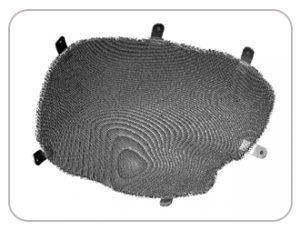

DEFECT FROM HEAD INJURY

IMPLANT FABRICATED USING 3D PRINTING TECHNOLOGY

POST-SURGERY SCAN IMAGE AFTER 24 MONTHS SHOWING PERFECT IMPLANT FIT